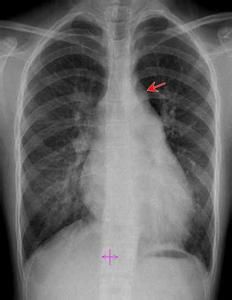

漏斗征是先心"動脈導管未閉"較為特異的徵象,表現為主動脈結下方的動脈壁向外膨隆,其下方降主動脈在與肺動脈段相交處驟然內收,主要是由於導管附著處主動脈壁的局部漏斗形膨出所致。